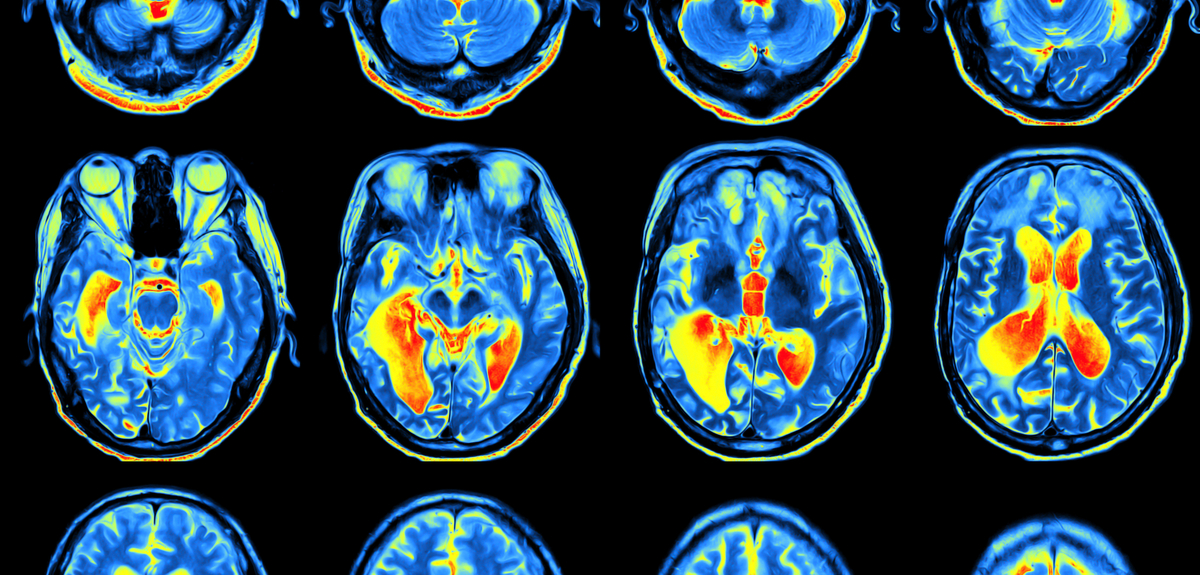

Use this free printable garden planner to organize all of your garden plans projects and records Study s MRI Images Suggest Fidgeting Good For ADHD Brain New Zealand

Study s MRI Images Suggest Fidgeting Good For ADHD Brain New Zealand